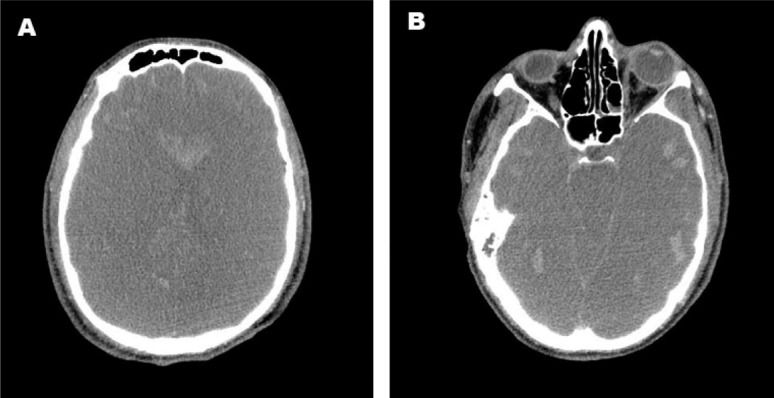

Twenty-four hours after arrival at Hospital das Clínicas, the patient's pupils became bilaterally dilated, and he lost brainstem reflexes in the absence of sedation, a clinical finding compatible with brain death. An apnea test was performed while the patient was normothermic with a mean arterial blood pressure of 86 mmHg by setting the ECMO to provide a pulse oximetry of at least 90% with the lowest sweeper flow setting. Mechanical ventilation was withdrawn, and continuous oxygen was supplied through the tracheal tube to prevent hypoxia. Close monitoring for respiratory movements was performed for 10 minutes. An arterial blood analysis was performed before and after the test to detect an increase in PaCO2 (Table 2). The neurological tests were repeated six hours later according to the Brazilian laws regulating the diagnosis of brain death. Transcranial Doppler ultrasonography indicated cerebral circulatory arrest, and computed tomography showed diffuse brain edema, brainstem herniation, and multiple foci of hemorrhage (Figure 2). Thus, ICU support was withdrawn.

The patient had a peripheral oxygen saturation of 80% and a PaCO2 of 80 mmHg without hemodynamic compromise. Mechanical ventilation was set at a PEEP of 10 cmH2O, an FiO2 of 1, and a peak pressure of 35 cmH2O. Venous-venous ECMO support was initiated. Her blood gas parameters improved after ECMO support, and the patient was transferred by helicopter. The entire process, from the initial call to arrival at Hospital das Clínicas, lasted four hours. The chest radiograph acquired in our hospital is shown in Figure 1b.